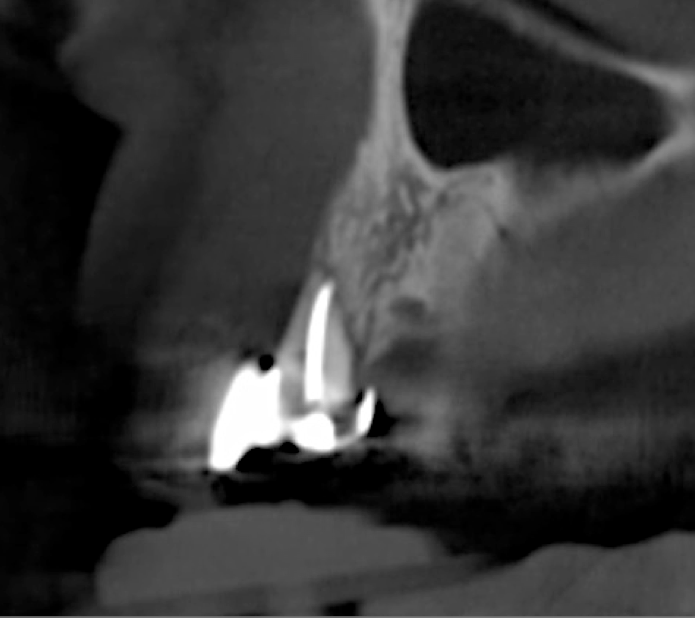

After 3 months of post-orthodontic stabilization, a cone-beam computed tomography scan was taken to re-evaluate the results and plan the future treatment sequence. Tomographic images clearly showed vertical gains in alveolar height, including in the edentulous area corresponding to tooth No. 7 (Figure 10 through Figure 12). The apex of tooth No. 8 was forced-erupted beyond its socket and could be visibly located within the soft tissue.30,33

Fig 10. Tomographic images of teeth Nos. 6 (Fig 10), 7 (Fig 11), and 8 (Fig 12) clearly showed vertical gains in alveolar height, including in the edentulous area corresponding to tooth No. 7. The apex of tooth No. 8 was located within the soft tissue because it was force-erupted beyond its socket.

Figure 10

Fig 11. Tomographic images of teeth Nos. 6 (Fig 10), 7 (Fig 11), and 8 (Fig 12) clearly showed vertical gains in alveolar height, including in the edentulous area corresponding to tooth No. 7. The apex of tooth No. 8 was located within the soft tissue because it was force-erupted beyond its socket.

Figure 11

Fig 12. Tomographic images of teeth Nos. 6 (Fig 10), 7 (Fig 11), and 8 (Fig 12) clearly showed vertical gains in alveolar height, including in the edentulous area corresponding to tooth No. 7. The apex of tooth No. 8 was located within the soft tissue because it was force-erupted beyond its socket.

Figure 12